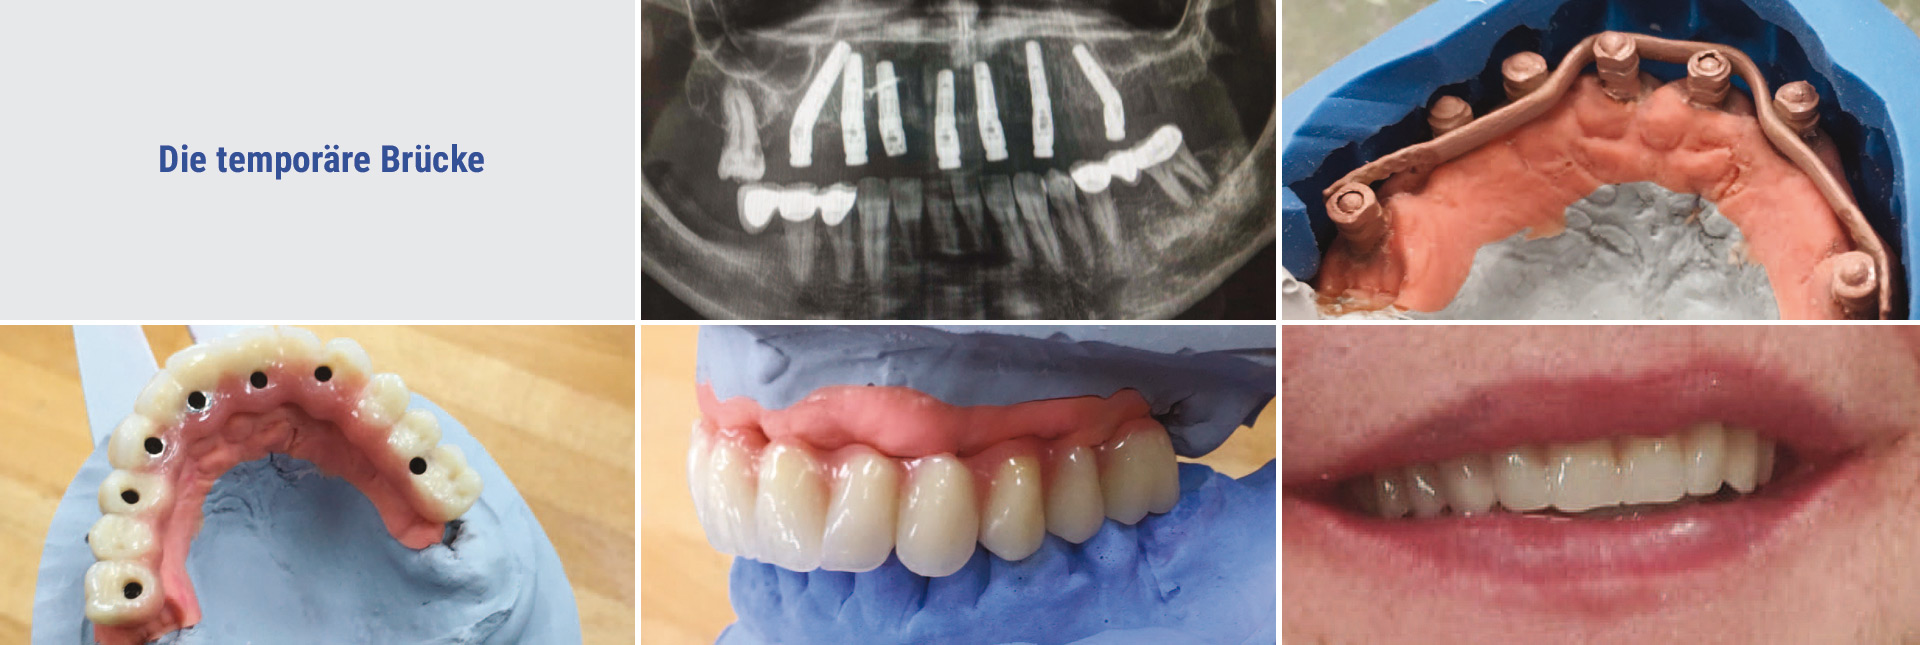

Die Herstellung der temporären Brücke

Nachdem die Implantate im Knochen verankert sind, wird ein Abdruck der Situation in das Labor geschickt. Die aufgestellten Zähne werden in Position gebracht und durch einen Metallbügel stabilisiert. Somit ist die Versorgung über die Einheilphase stabil und gibt ein sicheres Gefühl. Die temporäre Brücke wird aus Kunststoff erstellt und muss spätestens nach einem Jahr durch die endgültige Versorgung ersetzt werden.